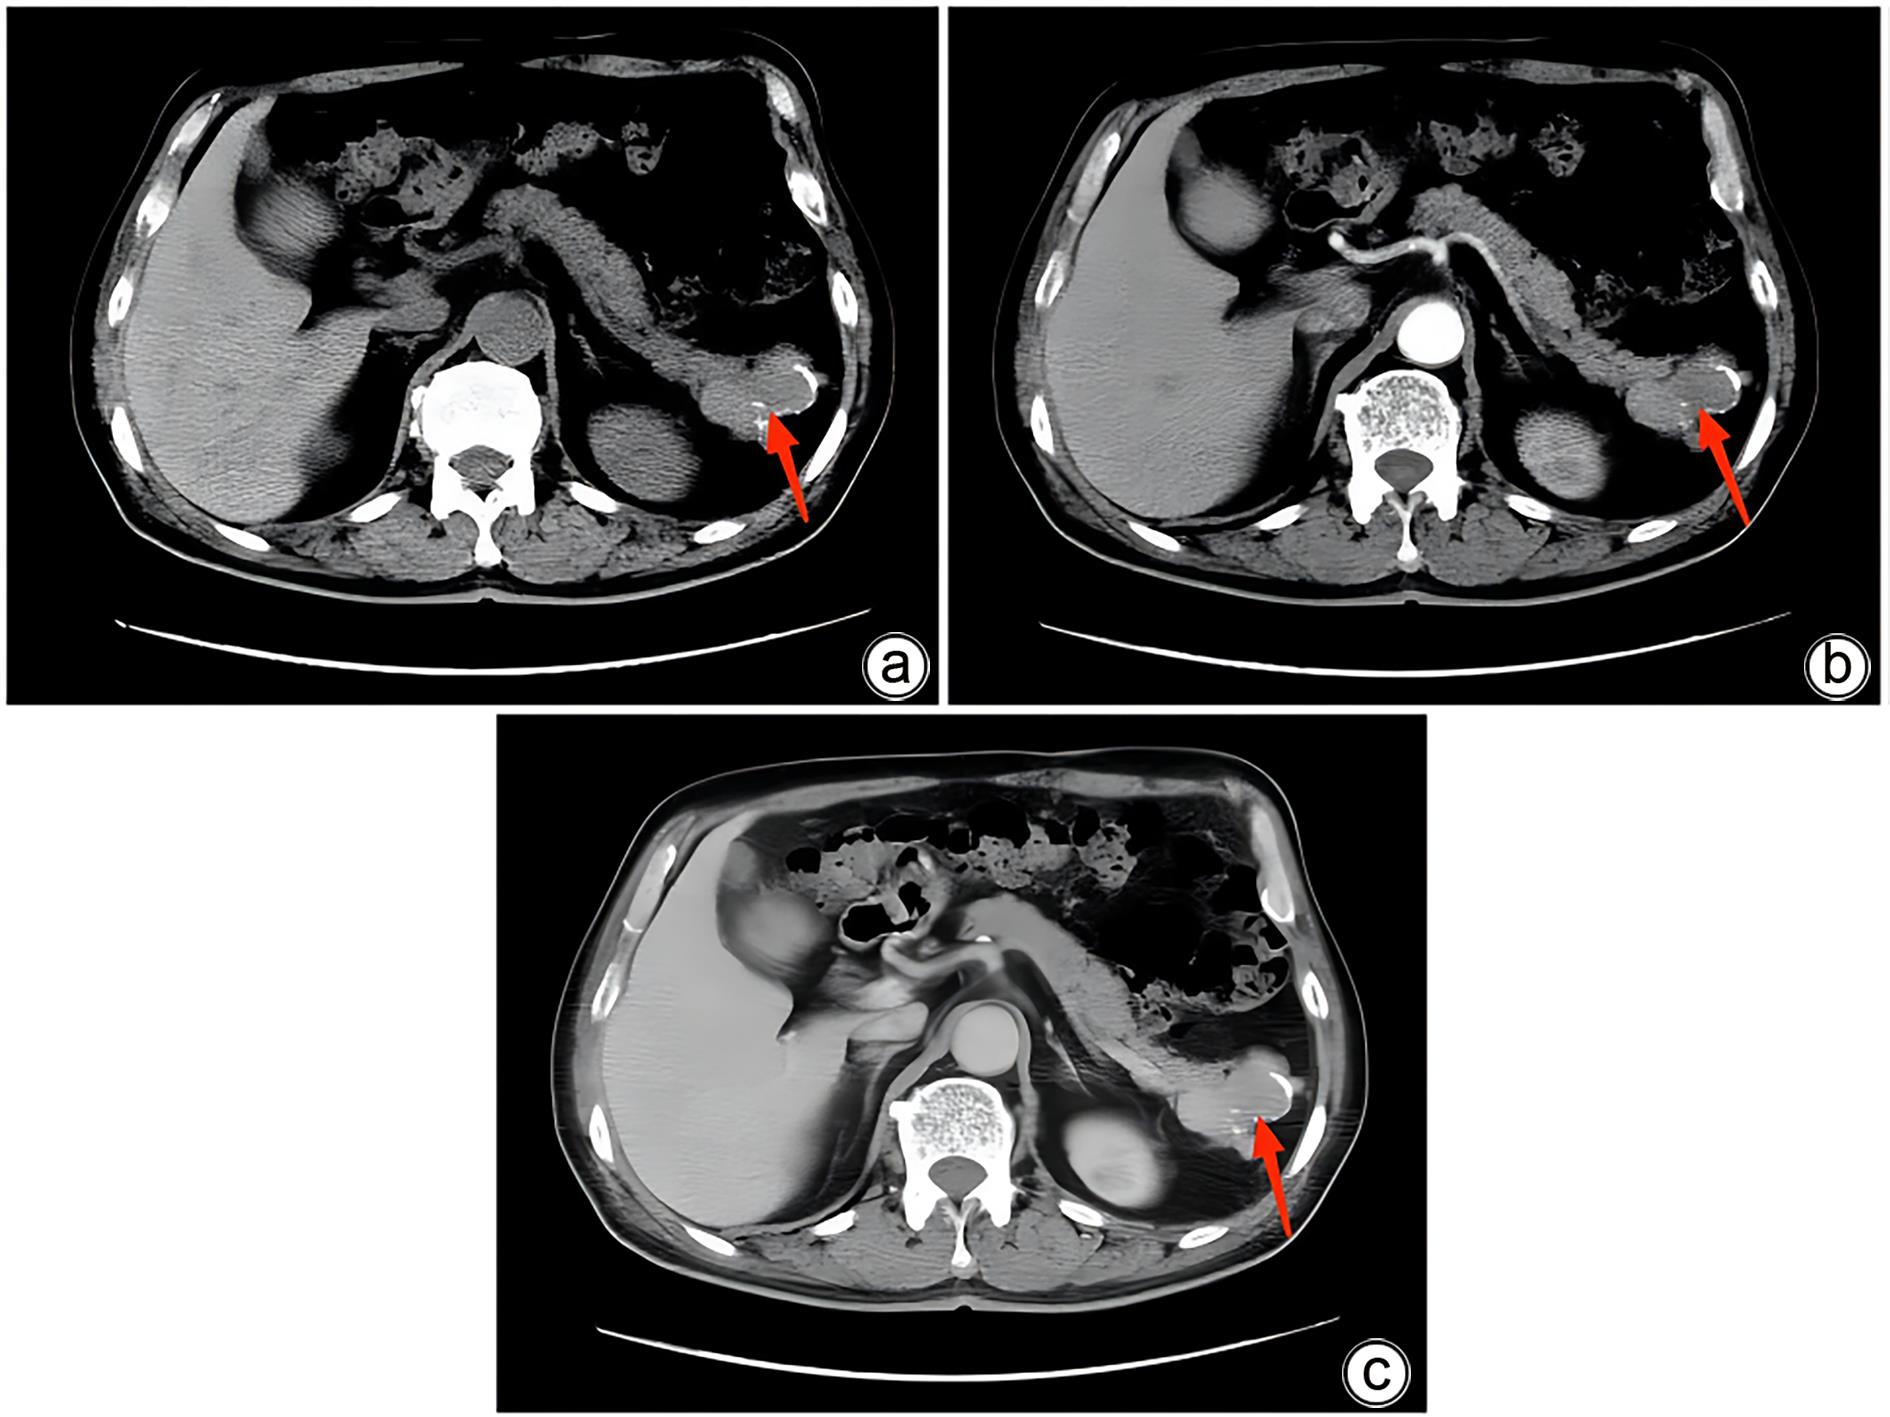

Misdiagnosis of intrapancreatic accessory spleen: A report of two cases

Mengzhe ZHANG, Jie RAO, Zhengle ZHANG

2024, 40(2): 365-368. DOI: 10.12449/JCH240223

Abstract(1274) HTML (315) PDF (1188KB)(59)

Abstract:

Accessory spleen refers to the spleen tissue that exists outside of the normal spleen, with a similar structure to the main spleen and certain functions. Intrapancreatic accessory spleen (IPAS) completely enveloped by the pancreas has an incidence rate of only 2%, and it is easily misdiagnosed in clinical practice due to its atypical clinical symptoms and similar radiological features to pancreatic neuroendocrine tumor, pancreatic solid pseudopapillary tumor, and other pancreatic space-occupying lesions. This article reports the clinical data of two patients with IPAS who were misdiagnosed as pancreatic neuroendocrine tumor and pancreatic solid pseudopapillary tumor, respectively, analyzes the reasons for misdiagnosis, and summarizes the experience in diagnosis and treatment, in order to improve the ability for the differential diagnosis of IPAS in clinical practice.